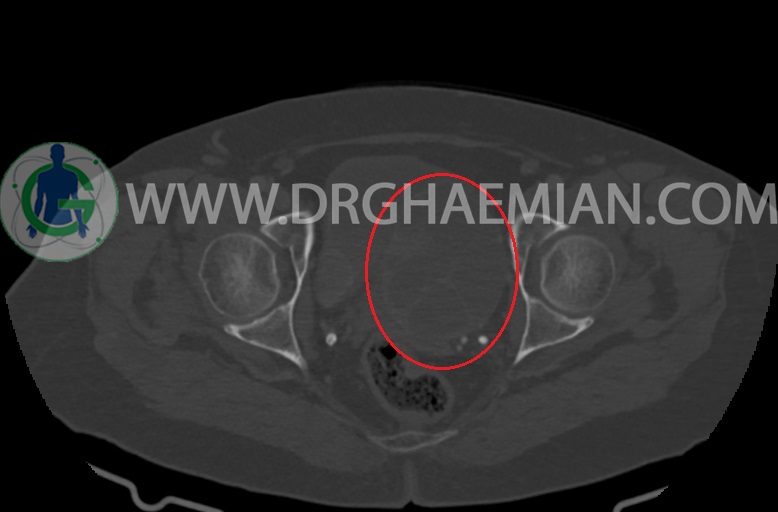

–ساختار Cystic multiseptate همراه با Enhancing thick septation به ابعاد 79x62mm در

لگن دیده می شود که در درجه اول مطرح کننده ی ضایعات نئوپلاستیک تخمدانی نظیر mucinous cyst adenocarcinoma است.

–شواهد هیسترکتومی

–ضایعه ی mass like هیپردنس- هتروژن به قطر 42mm در سمت راست لگن